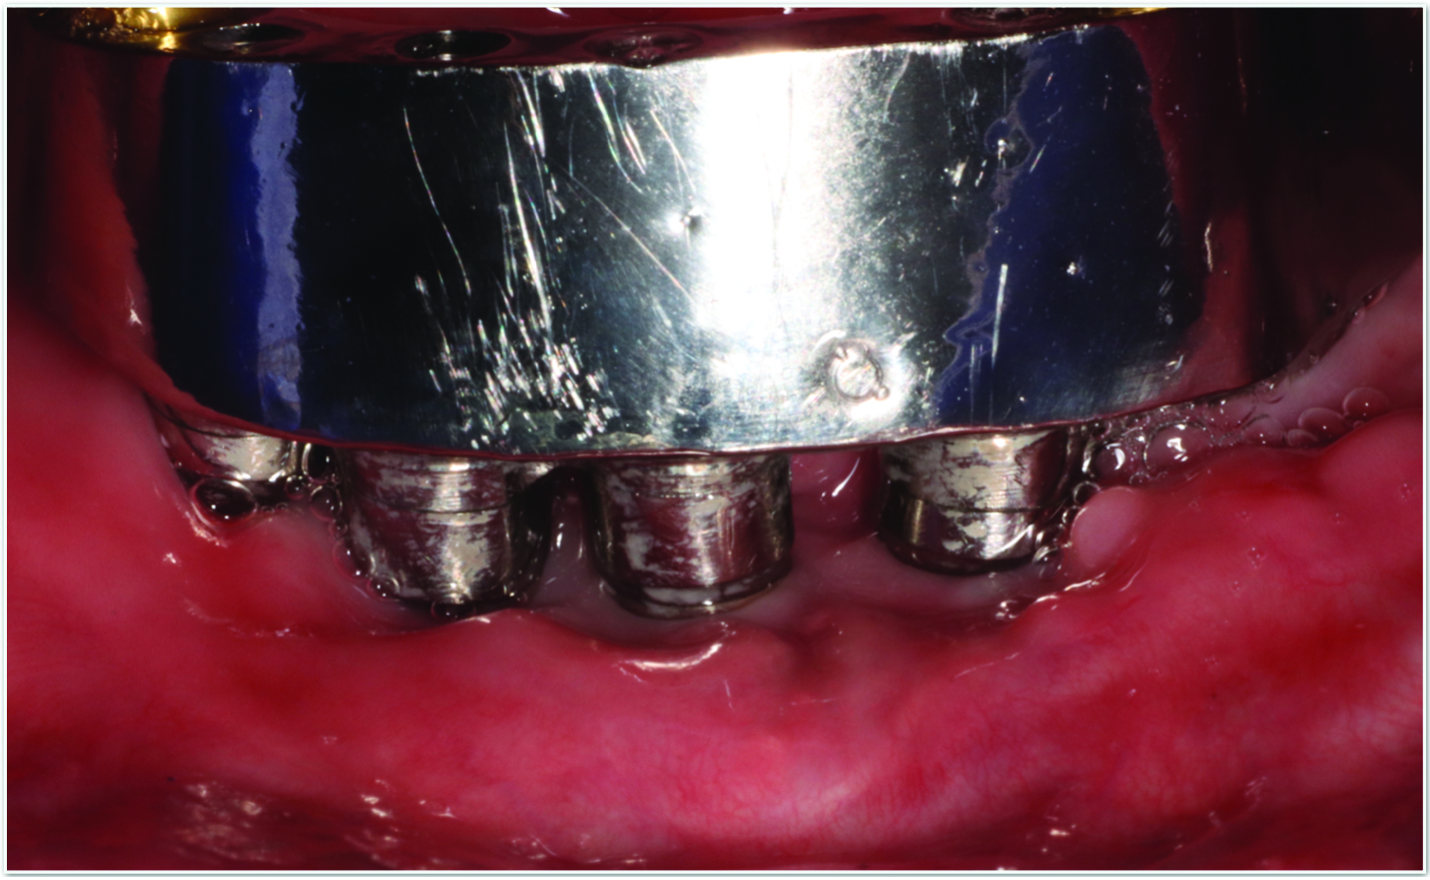

Fig 5 and Fig 6. Pre- (Fig 5) and post-treatment (Fig 6) photographs of a patient who received resective implant surgery to assess peri-implantitis at sites Nos. 14 and 15. Note the improved cleansability of the implants after surgery that opened the embrasure (Fig 6). The patient was placed on 3-month supportive peri-implant care post-surgery.

Figure 5

Figure 6